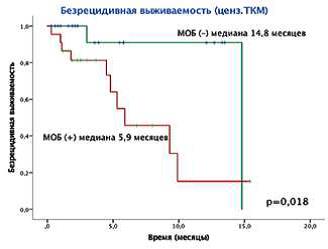

АААА-А20-120092490048-9. «Метод оценки уровня минимальной остаточной болезни (МОБ) у пациентов с впервые выявленным острым миелоидным лейкозом в постиндукционном периоде с помощью проточной цитофлуометрии». В результате проведенного исследования определена значимость достижения уровня МОБ менее 0,01 % после 1 курса терапии для прогнозирования развития раннего рецидива (в течение 6 месяцев) (61,5 % против 14,3 %, р = 0,002), снижения безрецидивной (5,9 месяца против недостижения медианы, р = 0,019) и общей (9,5 месяца против недостижения медианы, р = 0,032) выживаемости, в том числе в группах низкого и промежуточного генетического риска: медиана БРВ 6,75 месяца против недостижения медианы (р = 0,011) и медиана КЧР 5,28 месяца против недостижения медианы (р = 0,014). Применение разработанного метода прогнозирования течения заболевания и определения показаний к выполнению аллогенной ТГСК позволяет снизить частоту развития рецидива заболевания, оптимизировать программу терапии за счет сокращения количества курсов консолидации для пациентов с показаниями к алло-ТКМ и отказаться от использования высокотоксичного дорогостоящего метода лечения (ТГСК) в группе пациентов низкого и промежуточного риска с МОБ-негативным статусом после 1 курса терапии.